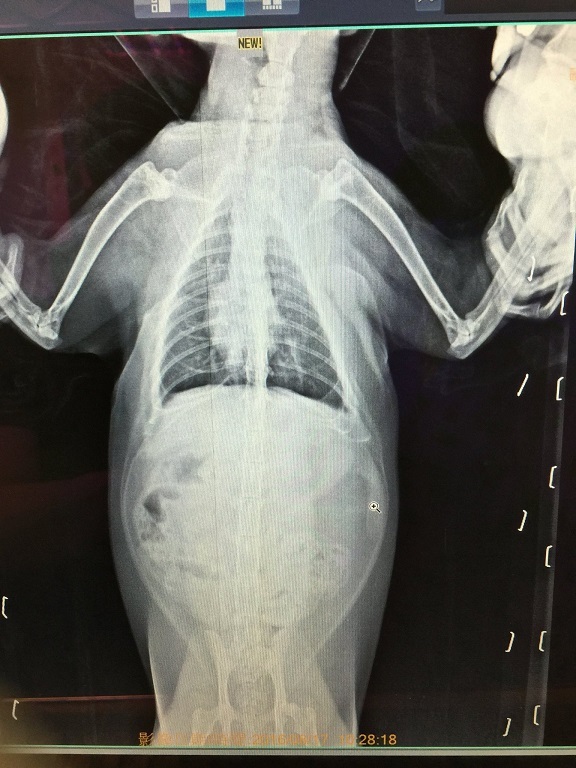

除了一般血檢、拍X光照之外,

另外也多驗了心絲蟲 (結果為陰性正常無心絲蟲感染)。

X光照片中支氣管和肺部都有稍微發炎的現象,

而血檢中比較不正常的是肝指數偏高,